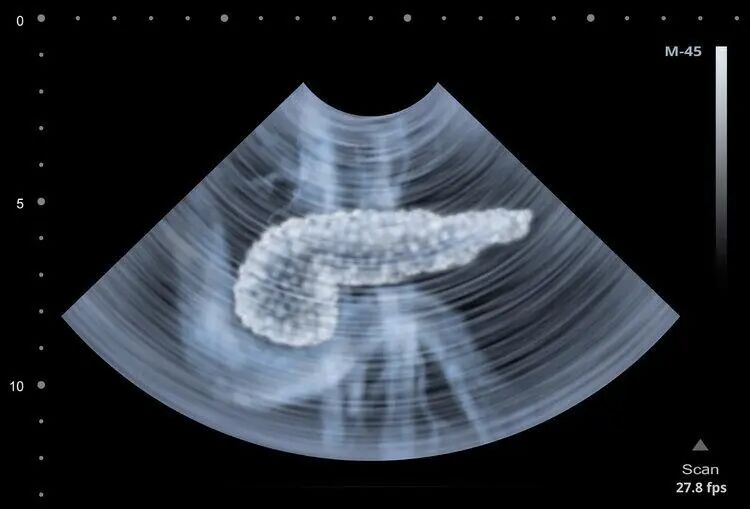

为了理解这一现象,我们需要了解胰腺的功能以及急性胰腺炎的发病机制。

胰腺是人体内的一个重要脏器,拥有内分泌和外分泌功能。其中,外分泌功能负责帮助消化,而内分泌则调节血糖水平。

胰腺的正常功能对维持身体健康至关重要。然而,在某些情况下,胰腺的功能平衡会被打破,从而导致急性胰腺炎的发生。